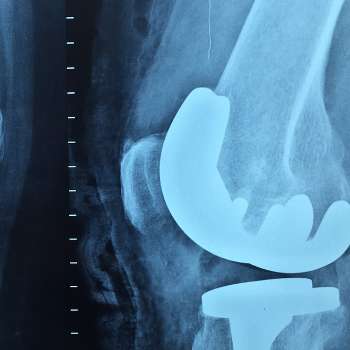

무릎에 물이 차는 원인 10가지 분석

무릎에 물이차요! 어느 날부터 무릎에 물이 차서 통증이 느껴집니다. 무릎에 물이 차는 이유에 대해 아주 자세히 알아보겠습니다.

무릎에 물이 차는 현상은 다양한 원인에 의해 발생할 수 있습니다. 아래는 무릎에 물이 차는 일반적인 10가지 원인에 대한 전문가적인 입장에서 상세히 설명한 것입니다.